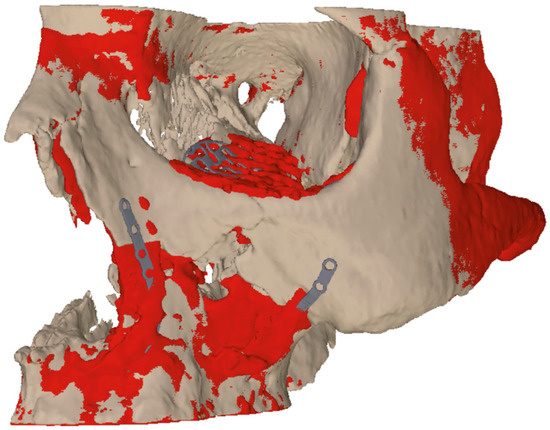

After repositioning and fixation of the four implants, an intraoperative 3D-Scan with a mobile 3D-C-arm device (Siemens Cios Spin®, Munich, Germany) was employed to prove reduction and implant position (Figure 5b,c). For postoperative evaluation we fused the 3D planning and the received result (Figure 6).

Figure 5. (a) Orbital implant inserted via a transconjunctival approach, (b,c) intraoperative 3D scan for implant placement control.

Figure 6. Image fusion of 3D planning (beige) and post-operative situation (red) to illustrate the difference between virtual planning and achieved result.